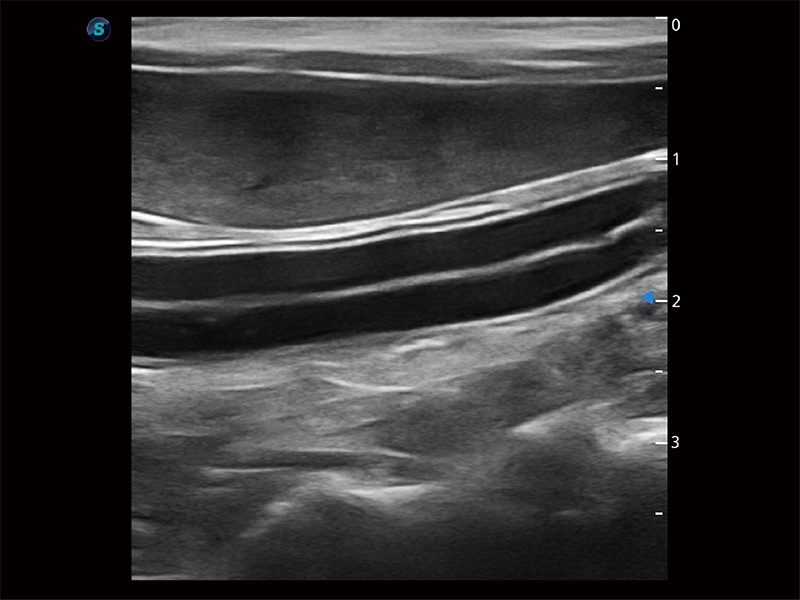

操作簡便,無需高頻度外力作用即可真實反映組織的形變,快速評估腫瘤良惡性。